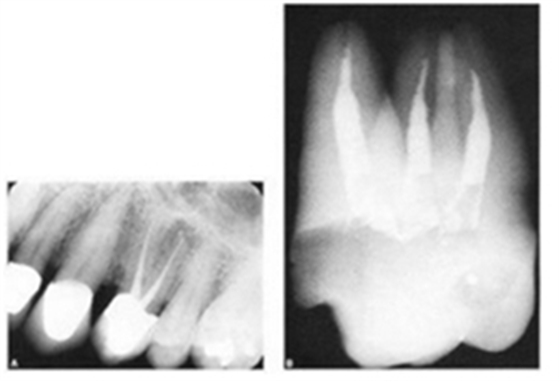

2.根管在x線片上是一種2維的圖像,所以雖然有時片子上表現(xiàn)為直的,但事實上根管是一個三維的空間,顯示沒有近遠中向的彎曲,卻可能向頰舌向彎曲,這種頰舌向彎曲的信息是平常臨床上無法獲得的。所以很少有完全直的根管。幾乎所有的根管都有一定程度的彎曲.尤其在根尖部。最后這句話幾乎可以當(dāng)作一個定理。我們看下面一張關(guān)于根尖孔的圖。

正常情況下根尖孔開口于根尖頂部(圖a),這是我們工作中最常見到的影像,但這種情況只有 56.53%,所以還有將近一半的情況是其他的開口形式。圖b就表明根尖孔的開口在唇舌向,當(dāng)我們見到這樣的根尖片的時候,要引起足夠的重視,有一個特殊的這種情況就是下第二磨牙“C”型根管的術(shù)后影像,常會有這樣的表現(xiàn)。這種研究國外并沒有做的很到位,因為他們很少遇到這種牙齒,到是黃種人的下7常見這種影像,國內(nèi)還是武漢研究的比較多。以后的內(nèi)容會有相關(guān)的討論。

圖3表明的內(nèi)容在這種示意圖上比較好懂,但臨床工作中,有醫(yī)生容易以為是自己側(cè)穿了,或者其他的什么情況,當(dāng)然根尖片拍的好壞也很有關(guān)系。